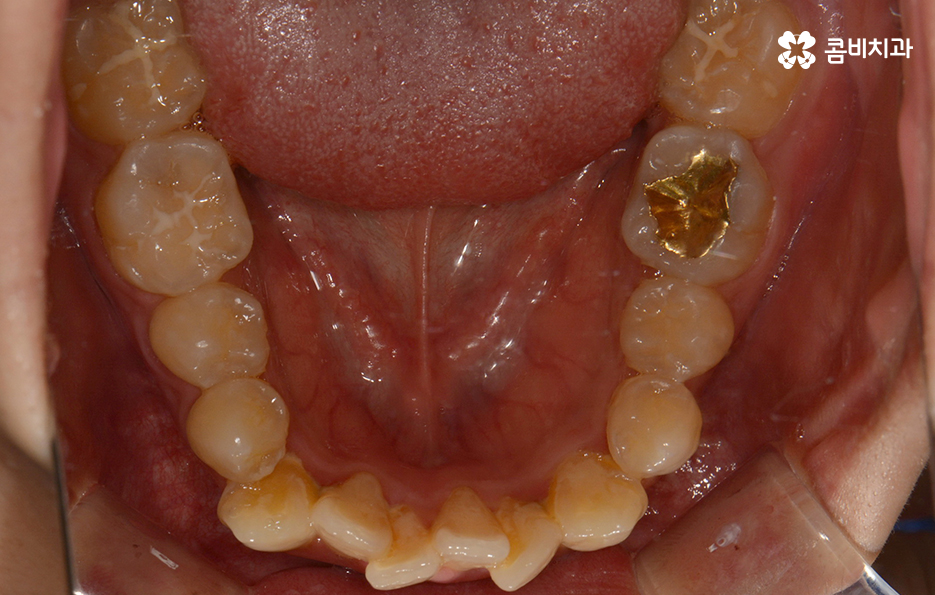

전체적으로 치열이 가지런한 편이지만 덧니가 하나 정도

눈에 띄게 있는 경우에는 귀여운 포인트로 여기는 경우도

있지만 덧니가 치아 곳곳에 심한 경우에는 웃을 때마다

콤플렉스를 느끼거나 치아 기능상의 문제, 청결 관리의

어려움 등을 느끼시는 분들도 많을 거예요.

덧니가 심한 경우에는 음식물이 치아 사이에 끼기 쉽고

심미적으로도 좋지 않기 때문에 덧니교정을 통해서

치열을 가지런하게 재배치하는 것이 필요할 수 있는데요.

왼쪽이 윗니이고 오른쪽이 아랫니인데 치열의 불규칙함이

심한 편이다 보니 평소 음식물이나 치석이 끼기 쉬운 환경이

되고 이러한 구강 환경이 지속된다면 충치와 잇몸질환의 발생률이 높아질 수 있어요.